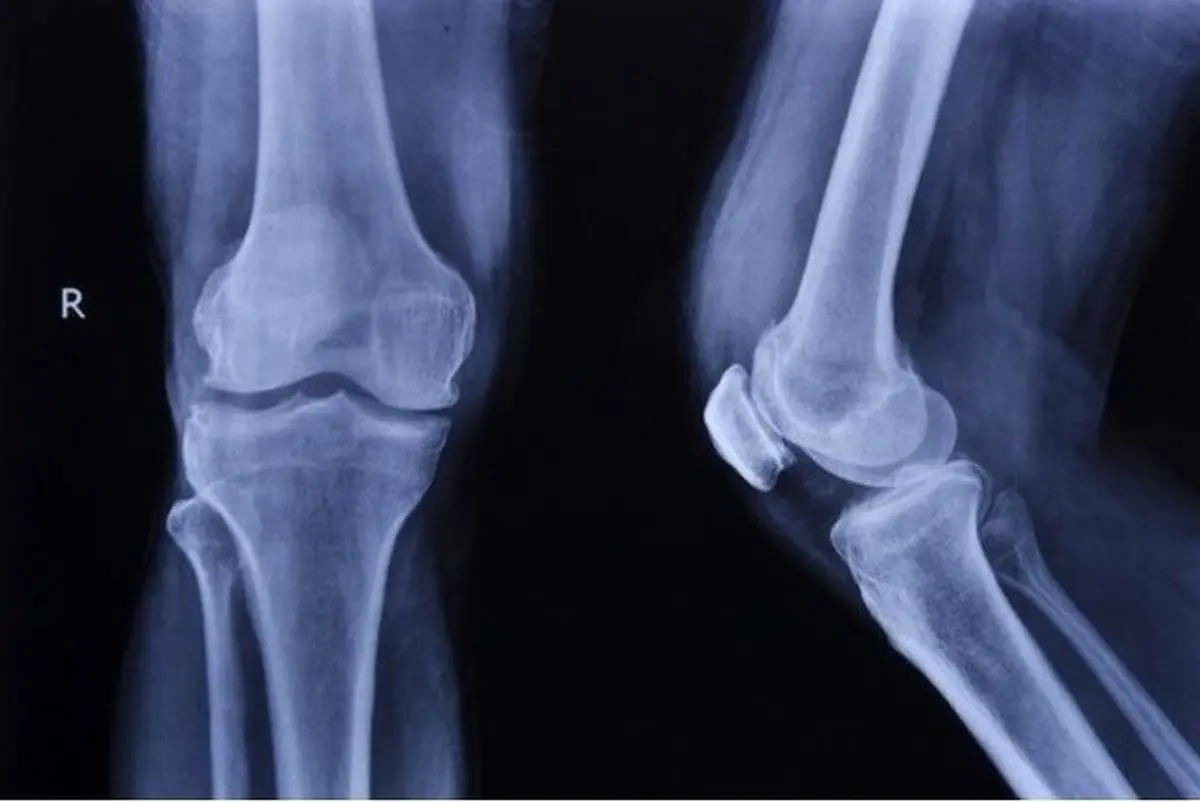

پژوهشگران دانشگاه صنعتی امیرکبیر به کمک چاپگرهای سه‌بعدی، داربست‌های استخوانی را طراحی کردند که قادر است با روش گرمادرمانی، برای درمان سرطان استخوان‌ در مجاورت بافت پیوندی به‌ کار برده شود.

سهمانی، ساخت این داربست را با استفاده از چاپگرهای سه‌بعدی و از ترکیب و سنتز بایوسرامیک (بردیجیت) و نانوذرات مغناطیسی (مگنتیت) دانست و ادامه داد: نتایج به دست آمده نشان داد که داربست تولید شده زیست سازگار بوده و خواص بیولوژیکی و مکانیکی مشابه با استخوان طبیعی دارد و از تخلخل لازم برای رشد سلول‌های استخوانی جهت ترمیم و بازسازی یک بخش صدمه‌ دیده‌ استخوان برخودار است.

مجری طرح با اشاره به کاربردهای داربست تولید شده، خاطر نشان کرد: از این داربست می‌توان در بخش مهندسی پزشکی، جهت ترمیم و بازسازی بخش‌های صدمه‌ دیده‌ استخوان بهره گرفت. از طرفی به دلیل دارا بودن نانوذرات مغناطیسی (مگنتیت) این قابلیت را دارد که با قرار گرفتن در یک میدان مغناطیسی AC، گرما تولید کند و سبب افزایش درجه حرارت بافت اطراف خود شود.

به گفته وی، افزایش دما در اطراف داربست موجب می‌شود تمامی سلول‌های سرطانی موجود در اطراف داربست جایگذاری شده در بافت، توسط هایپرترمیا (گرمادرمانی) از بین بروند.